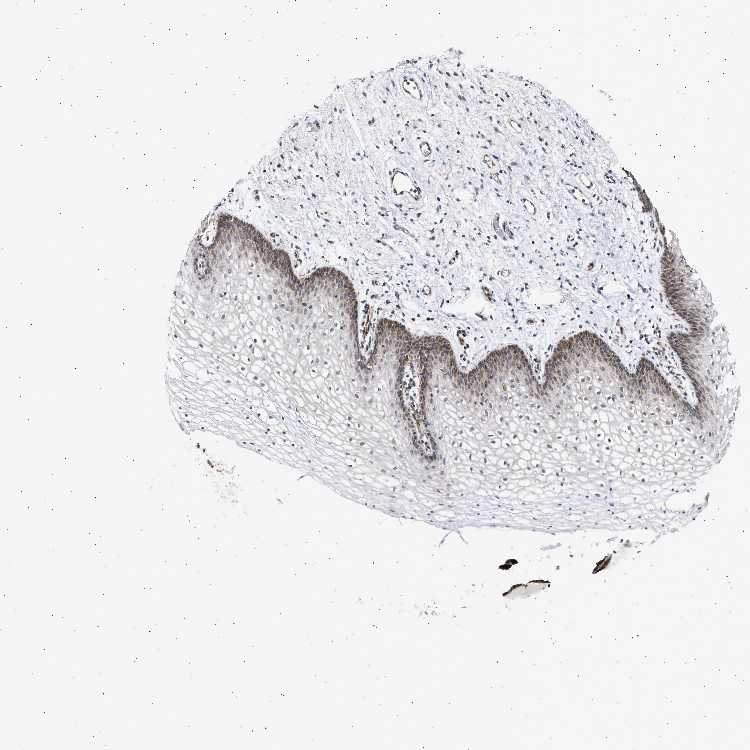

VAGINA - Antibody stainingi

Antibody staining in the annotated cell types in the current human tissue is reported as not detected, low, medium, or high, based on conventional immunohistochemistry profiling in selected tissues. This score is based on the combination of the staining intensity and fraction of stained cells.

Each image is clickable and will lead to virtual microscopy that enables deeper exploration of all samples and also displays staining intensity scores, fraction scores and subcellular localization as well as patient and tissue information for each sample.

Antibody HPA021798Antibody HPA022002Antibody HPA022992

Squamous epithelial cells LowLowMedium